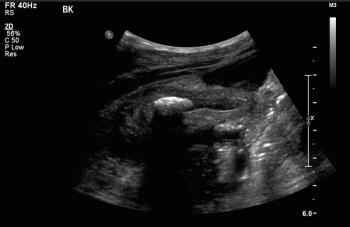

9-year-old male presents with acute onset abdominal pain with fever, vomiting, and diarrhea.